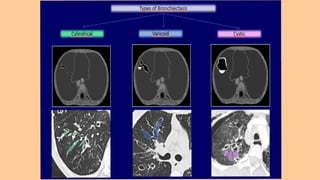

Classification Of Bronchiectasis On

The Basis Of Morphology :

1. Cylindrical bronchiectasis: bronchi are enlarged and cylindrical.

2. Varicose bronchiectasis: bronchi are irregular with areas of

dilatation and constriction.

3. Saccular or cystic: dilated bronchi form clusters of cysts. This is

the most severe form of bronchiectasis and is often found in patients

with cystic fibrosis

Classification Of BronchiectasisOn The Basis Of Morphology : 1. Cylindrical bronchiectasis: bronchi are enlarged and cylindrical. 2. Varicose bronchiectasis: bronchi are irregular with areas of dilatation and constriction. 3. Saccular or cystic: dilated bronchi form clusters of cysts. This is the most severe form of bronchiectasis and is often found in patients with cystic fibrosis